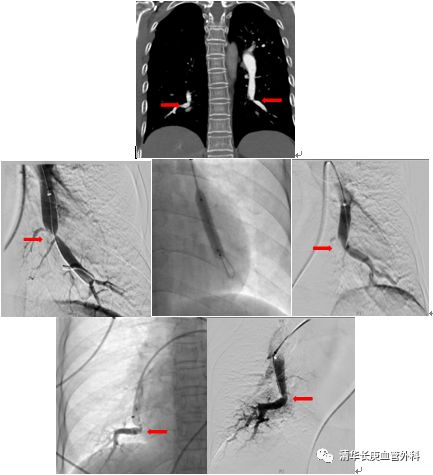

(术前双侧肺动脉主干内血栓,术中溶栓后改善,术后复查主干血栓消失)

北京清华长庚医院血管外科团队在吴巍巍主任的带领下,联合多科讨论后决定采用肺动脉球囊扩张成形术治疗通过右侧股静脉入路,选择进入患者左侧肺动脉基底段狭窄部位,完成肺动脉球囊成形术,球囊扩张后肺动脉形态改善。患者术后在监护病房观察一天后顺利返回普通病房,患者恢复顺利。一周后再次行右侧肺动脉基底段球囊扩张。患者术后6分钟步行距离明显提高,术后2天即可行走450m,肺动脉压力由术前82mmHg降至8mmHg6 。患者顺利出院,由于双侧肺动脉病变广泛,此后还将密切随诊,择期再次行其余部位的肺动脉腔内治疗。

双侧肺动脉基地段狭窄,球囊扩张前后对比